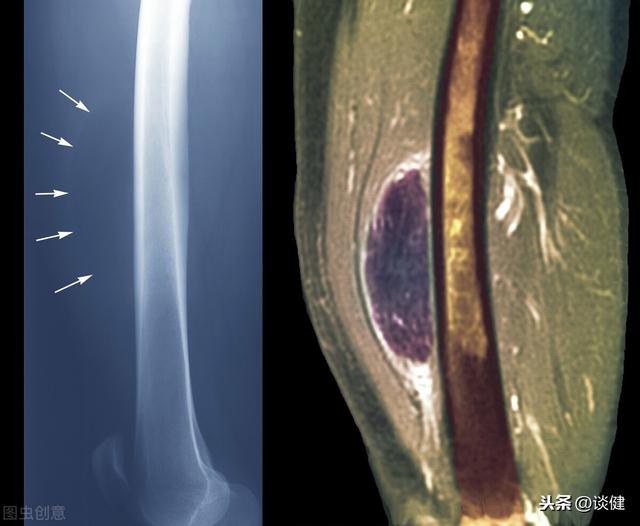

カラー超音波検査における脂肪腫

脂肪腫は良性の腫瘍であるが、同じような変化を持つ他の悪性腫瘍によるものかどうかを除外する必要がある。腫瘤の周囲に血液が流れ込み、重要な神経や血管が集積している場合は、悪性腫瘍の可能性があるため注意が必要である。肉眼的検査、触診、超音波検査、さらには病理組織学的な腫瘍の組成分析によって、確定診断を下すことができる。結局のところ、たとえ小さな病気であっても、私たちは結論を急がず、厳密であるべきなのである。